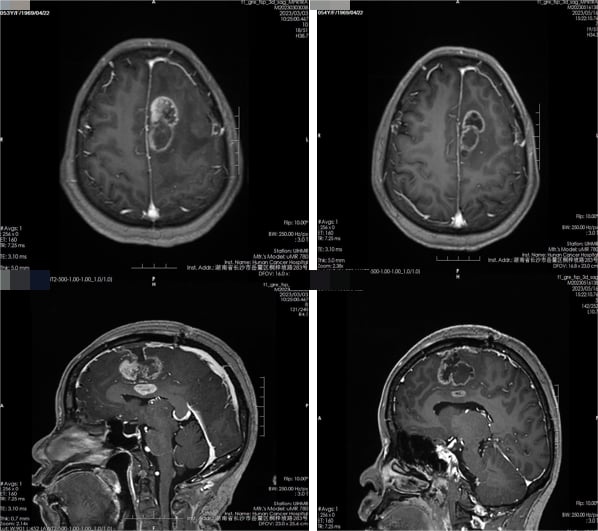

患者为一名54岁女性,确诊为脑胶质瘤(WHO IV级,胶质母细胞瘤)。她接受了标准的一线治疗方案:手术切除肿瘤,术后辅以放疗和同步口服替莫唑胺化疗。初期治疗效果良好,影像学检查显示肿瘤缩小,病情得到控制。

图1. 放疗前后脑MR平扫检查结果(左:治疗前;右:治疗后)